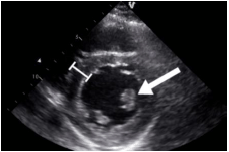

Observe a imagem:

O músculo papilar identificado na seta é o